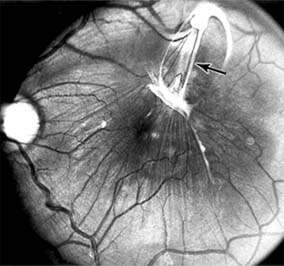

Figure 10-7

Figure 10-7: Late fluorescein leakage from macular subretinal neovascularization in a patient with presumed ocular histoplasmosis syndrome.

Presumed Ocular Histoplasmosis Syndrome (Figures 10-5, 10-6 and 10-7)

In this disease, serous and hemorrhagic detachments of the macula are associated with multiple peripheral atrophic chorioretinal scars and peripapillary chorioretinal scarring (see Chapter 7). The syndrome usually occurs in healthy patients between the third and sixth decades of life, and the scars are probably caused by an antecedent subclinical systemic infection with Histoplasma capsulatum. The macular detachments are due to subretinal neovascularization, and the visual prognosis depends on the proximity of the neovascular membrane to the center of the fovea. If the membrane extends inside the foveal avascular zone, only 15% of eyes will retain 20/40 vision. A macular scar may change over time, and 10% of patients with normal maculae will develop new atrophic scars in this region. The relative risk of developing macular subretinal neovascularization in the second eye of an affected patient is significant, and these patients should be instructed in the frequent use of the Amsler grid and the importance of prompt examination when changes are detected.